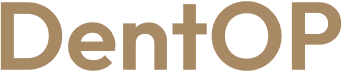

Boala parododontală agresivă i-a distrus dantura, dar procedura ,,Dantură Fixă în 24h pe implanturi dentare” i-a salvat încrederea de sine și zâmbetul. Domnul T. a trecut printr-o intervenție complexă de inserare a 10 implanturi dentare într-o singură ședință.

După 24h de la intervenție, domnul T. s-a prezentat din nou la clinică pentru a-i fi fixate lucrările provizorii, lucrări pe care le-a purtat timp de 4-6 luni și care l-au ajutat să mănânce și să zâmbească.

După această perioadă, pacientului i-au fost fixate lucrările finale, lucrări concepute special pentru fizionomia sa. La alegerea acestora, domnul T. și-a exprimat preferințele și nevoile legate de aspectul final al dinților.